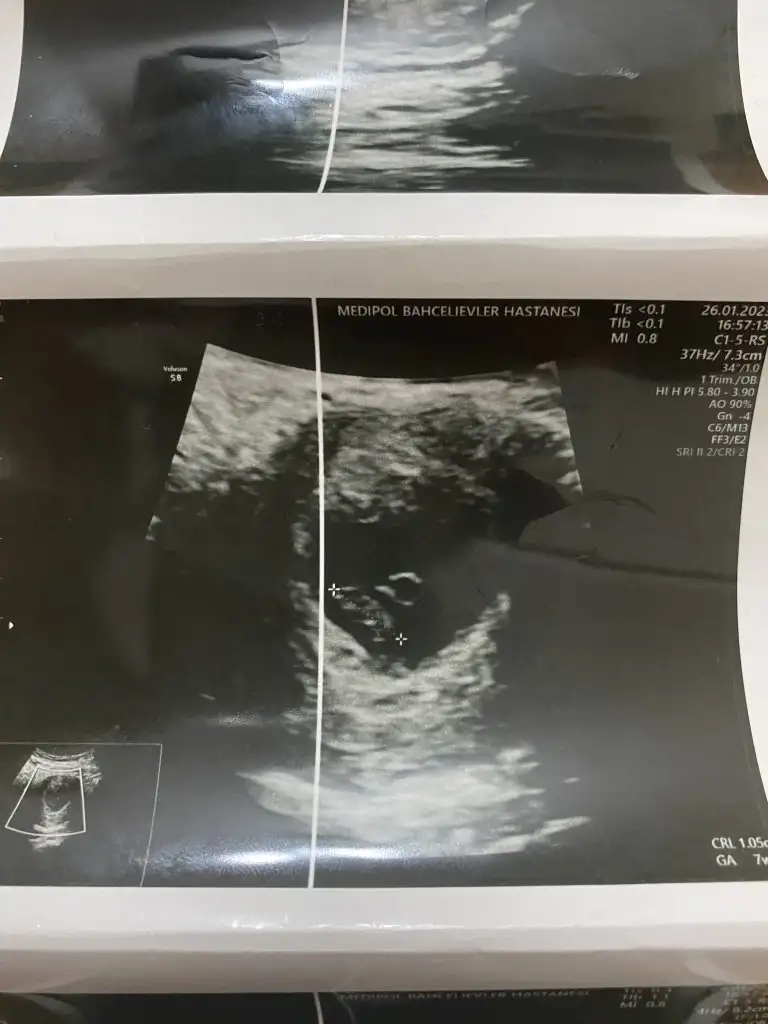

Banada tahminde bulunur musunuz lutfeen 8+3 ultrasonda karından ultrason bu arada

Merhaba 11e 4 haftalık cinsiyeti nedir yorumunuzu bekliyorum.